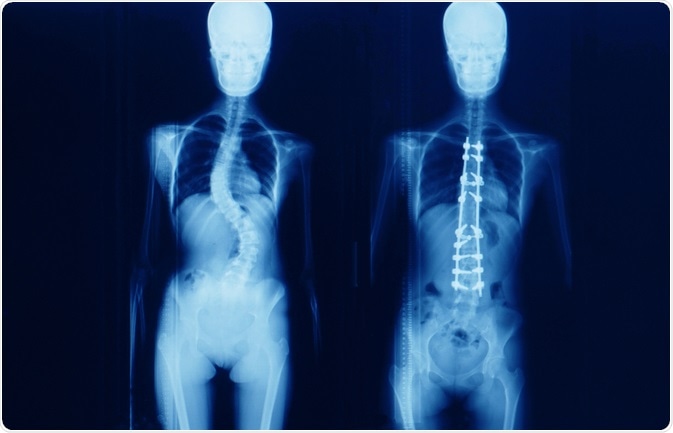

Surgery is usually able to correct the curvature of the spine significantly, but it is rare for the spine to become completely straight as a result of the surgery.

Spinal fusion is the most common surgery for patients with scoliosis that have finished growing and involves a graft of bone onto the spinal vertebrae that eventually heal together to form a solid, rigid mass of bone. Although this process may restrict the movement of the spine, it prevents the curvature from becoming worse and may correct severe cases.

There are two main techniques that may be used: anterior fusion provides access to the spine via an incision on the side of the chest wall, and posterior fusion utilizes an incision on the back and metal instruments for the curve correction. The bone graft can be attached to the spine with a combination of metal rods, screws, hooks and wires, which are left in place permanently.